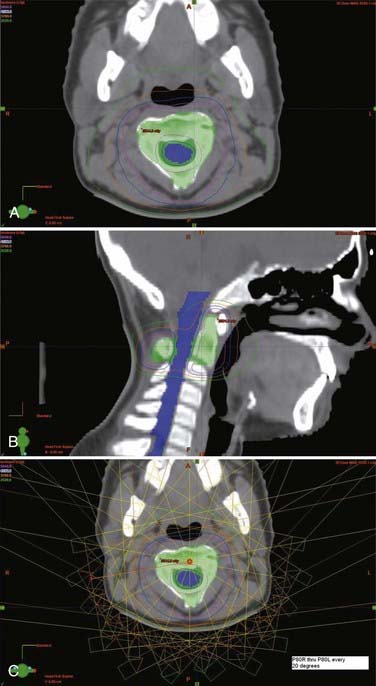

The radiotherapy dose and techniques for intramedullary ependymomas are similar to those for astrocytomas (see earlier). CTV is generally defined as a 1- to 2-cm margin on residual tumor on T1-weighted contrast-enhanced MRI plus any edema seen on T2-weighted or fluid-attenuated inversion recovery (FLAIR) sequences. As with astrocytomas, a more generous CTV is recommended for malignant and infiltrative tumors. If no residual tumor is visible, the postoperative cavity (which preoperative imaging can help delineate) is considered the GTV. A total dose of 45 to 50.4 Gy is typically given in 1.8- to 2-Gy daily fractions to the CTV, along with a boost for a total dose of 54 to 55.8 Gy to areas of bulky residual disease (GTV) (Fig. 252-1).

Treatment of myxopapillary ependymomas is similar to that for intramedullary tumors (see the earlier sections on astrocytoma and ependymoma). The treatment field should be extended to encompass the entire thecal sac, with the field widened inferiorly to the sacroiliac joints to ensure adequate coverage of the meningeal sleeves within the intervertebral foramina (CTV). Failure to adequately encompass the thecal sac has been associated with an increased rate of treatment failure.35 The lateral beam technique described earlier adequately covers lateral cerebrospinal fluid extension of the thecal sac within the sacrum and minimizes the dose to the pelvic organs. A total dose of 45 to 50.4 Gy is typically given in 1.8- to 2-Gy daily fractions to the CTV, along with a boost for a total dose of 54 to 55.8 Gy to areas of bulky residual disease (GTV).